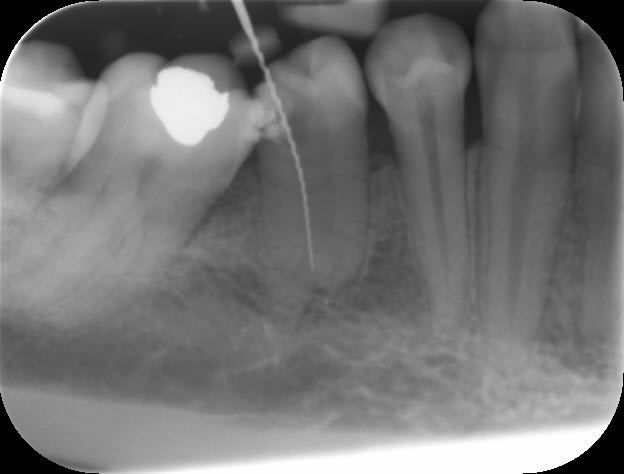

Bon...on va attendre 6 mois avant de dire qu'il n'y a pas de soucis. La difficulté ici était le lentulo fracturé coronairement qui n'autorisait pas le by-pass (au départ, parce que je lui ai expliqué qu'il fallait qu'il se pousse pour me laisser passer et il a été gentil, il m'a obéit :-))

En fait, ça ne se voit pas sur la radio d'eugenol (perte de qualité) mais il y a un lentulo dans l'obturation du canal MV (et un autre au niveau apical que l'on voit ici).

Pour répondre à dumaille : oui. Si tu regardes bien la radio postop, tu verras des trabécules osseuses juste sous la furcation. Le sondage était normal aussi bien en lingual qu'en vestibulaire. La lésion étant fermée, il n'y a aucune raison qu'en cas de succès apical il y ait une persistance radioclaire entre les racines.

Pour Aymen : Une fois le by-pass réalisé, Dominique Martin conseillait il y a quelques années dans une conférence de la SOP de rester en manuel avec les instruments NiTi. Je ne sais pas s'il s'applique ça à lui même ou si c'était un conseil destiné aux praticiens lambdas. Personnellement, je prend souvent ce risque (si je sens intuitivement en fonction du cas que je peux le faire, et si j'ai le moindre doute, je pense à mon ami Willy qui me disait un jour "si tu te poses la question, ne le fais pas !" Je pense d'ailleurs souvent à lui à cause de ça car il y a plein de situations cliniques où je me pose des questions. Dans le cas présenté, j'y suis allé en rotation mécanique justement. L'instrument fracturé coronairement à été enlevé après la mise en forme. Il faut bien comprendre qu'ici, ce fragment était un lentulo. Si ça avait été un protaper F2 par exemple, je serai sans doute rester en manuel, en fonction des sensations tactiles avec le dernier instrument acier utilisé (ici une lime K15).

Pour l'obturation, je ne vois aucune raison de changer quoique ce soit à cause d'un fragment d'instrument qui resterait en place. Une technique à chaud me parait cependant idéale pour enrober le fragment. Dans le cas présent, c'était thermafil et la courbure apicale en était une excellente indication à mon avis.